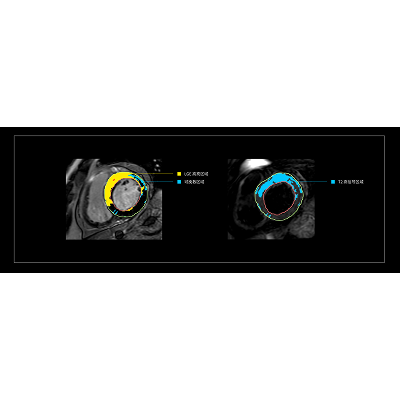

联影智能MR心脏智能分析系统可覆盖多序列的心脏磁共振,支持实时编辑心肌追踪。目前,该系统涵盖心功能、心应变、T1 Mapping、LGE/T2W、MR灌注分析等多个序列,可一站式覆盖心脏形态、功能、结构、组织特征等多维度数据,大幅提升临床诊断效率,有望推动我国CMR检查实现更广泛的应用,让更多心脏疾病患者受益。